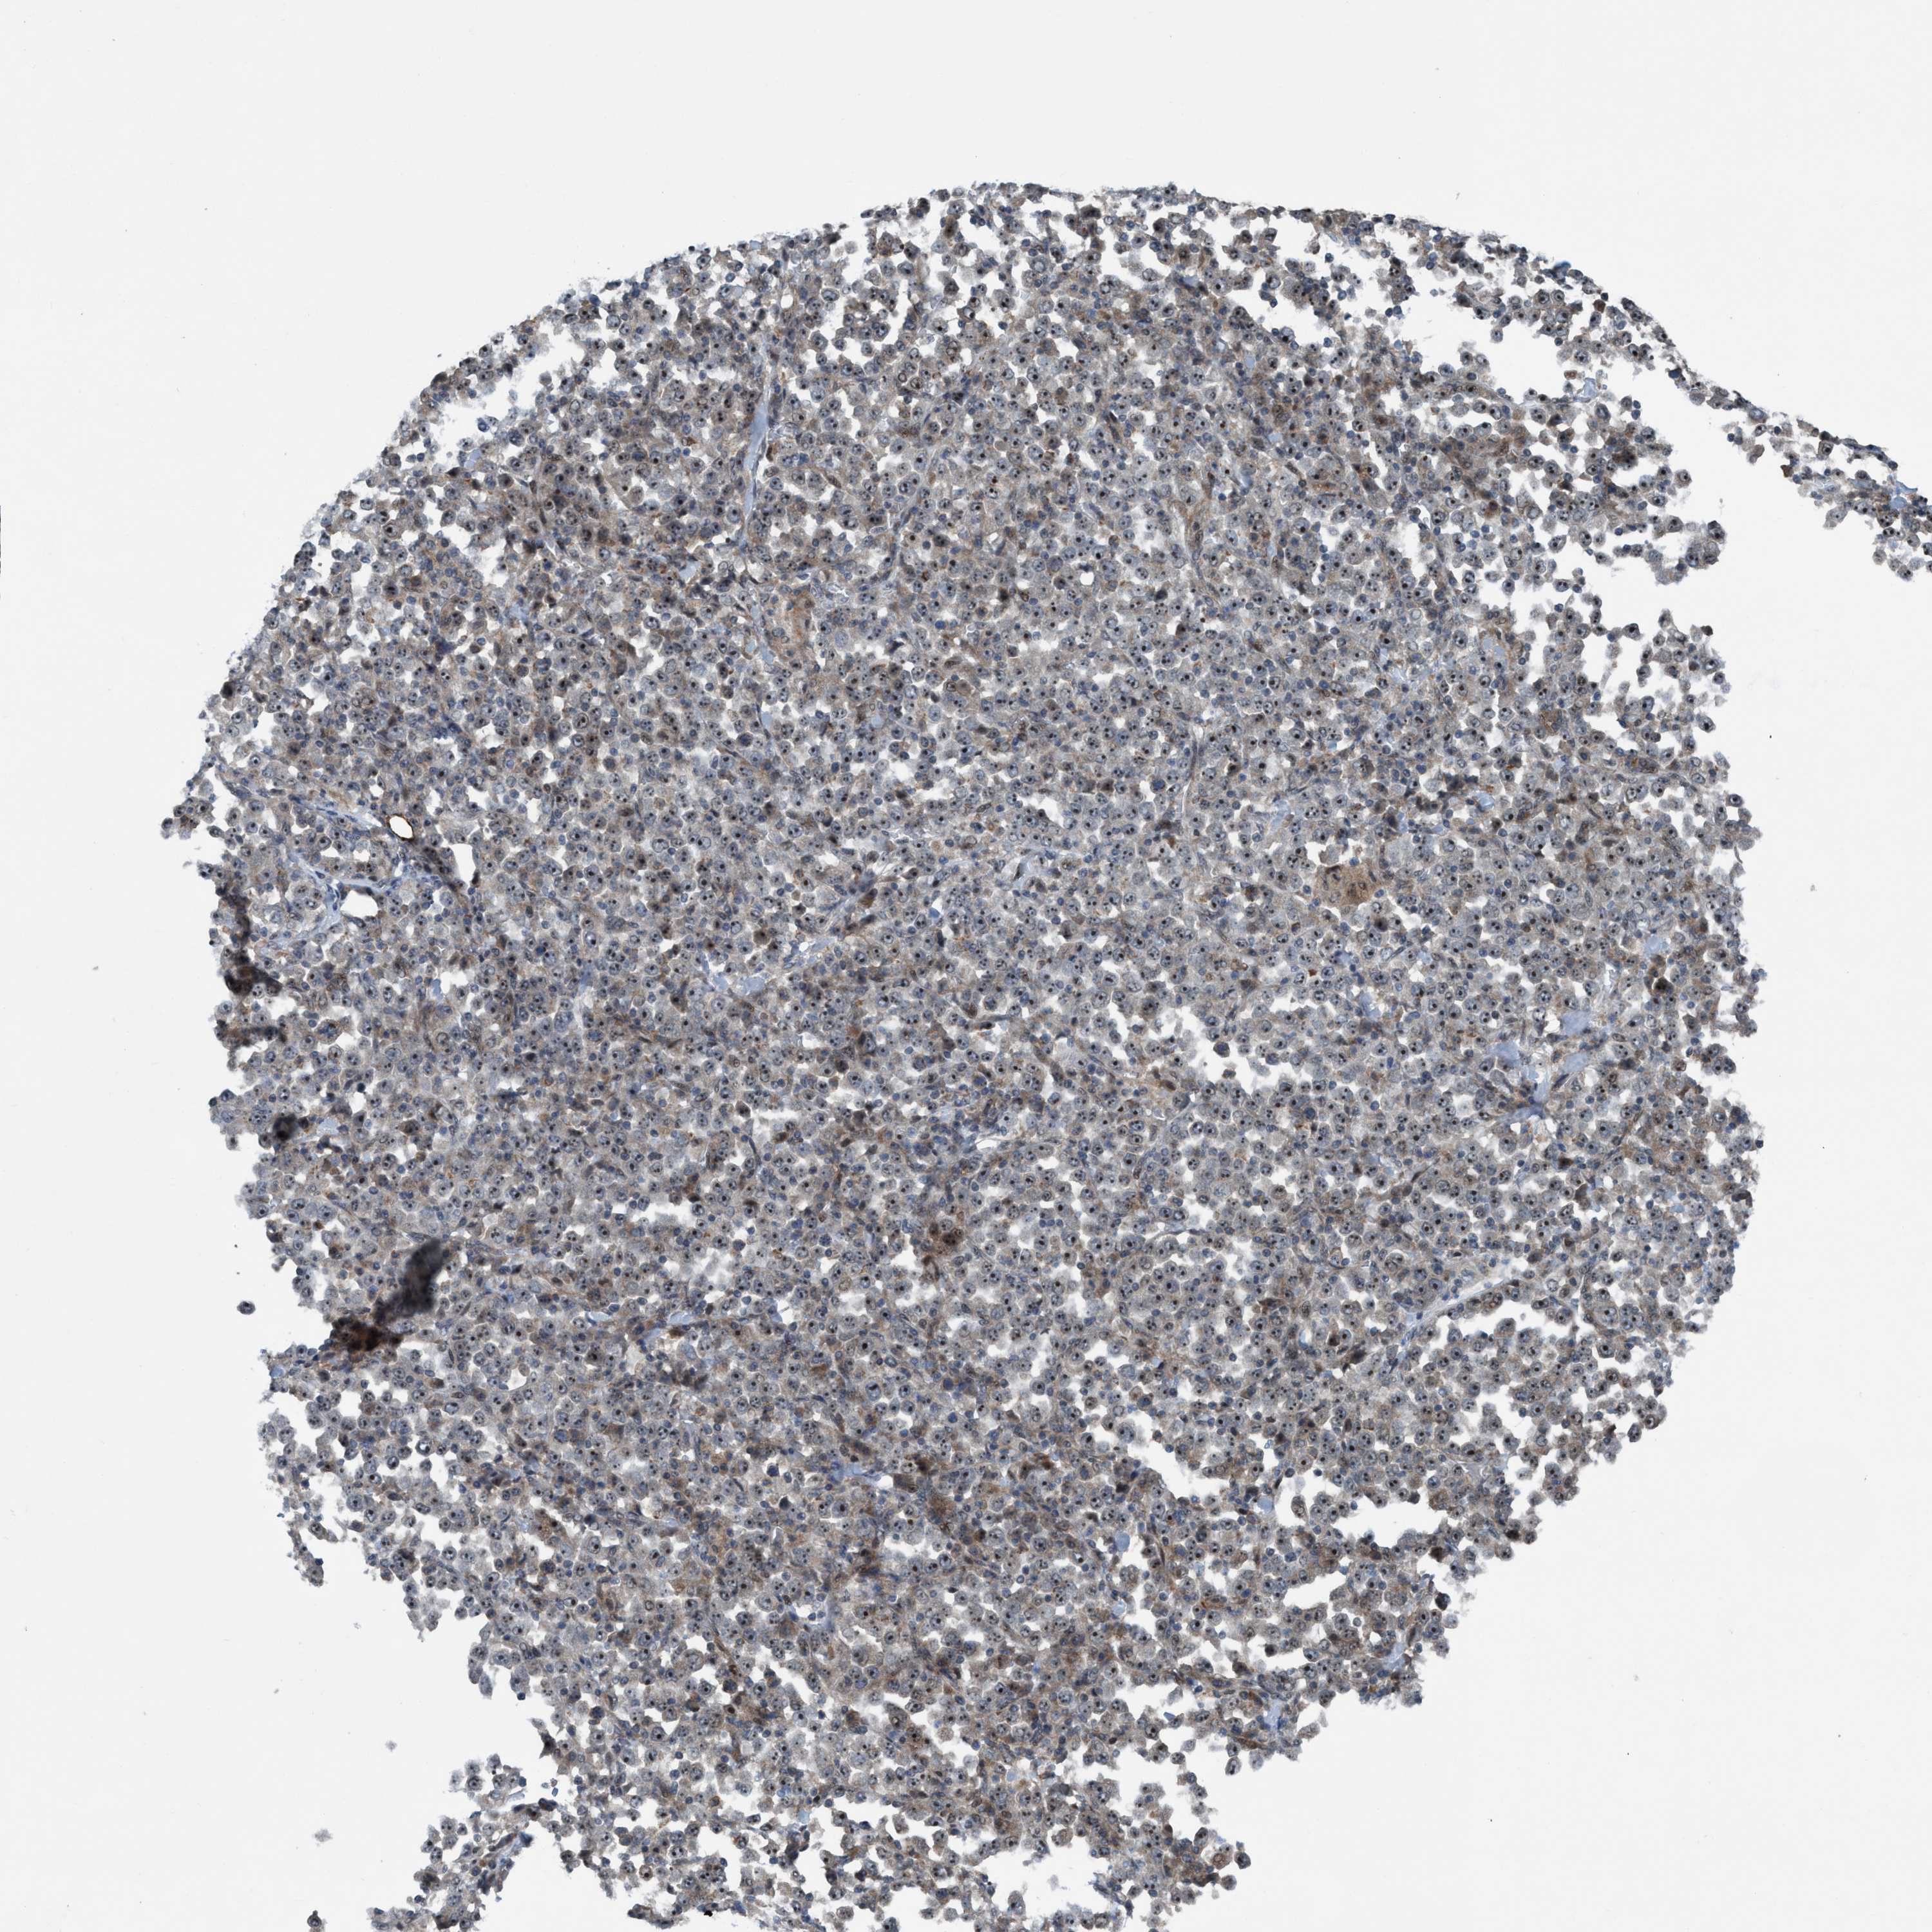

STOMACH CANCER - Protein expressioni

A mouse-over function shows sample information and annotation data. Click on an image to view it in a full screen mode. Samples can be filtered based on level of antibody staining by selecting one or several of the following categories: high, medium, low and not detected. The assay and annotation is described here.

Note that samples used for immunohistochemistry by the Human Protein Atlas do not correspond to samples in the TCGA dataset.

Antibody stainingi

Antibody staining in the annotated cell types in the current human tissue is reported as not detected, low, medium, or high, based on conventional immunohistochemistry profiling in selected tissues. This score is based on the combination of the staining intensity and fraction of stained cells.

Each image is clickable and will lead to virtual microscopy that enables deeper exploration of all samples and also displays staining intensity scores, fraction scores and subcellular localization as well as patient and tissue information for each sample.

Antibody HPA023189

Staining

High

Medium

Low

Not detected

Intensity

Strong

Moderate

Weak

Negative

Quantity

>75%

75%-25%

<25%

None

Location

Nuclear

Cytoplasmic/membranous

Cytoplasmic/membranous,nuclear

Adenocarcinoma, NOS